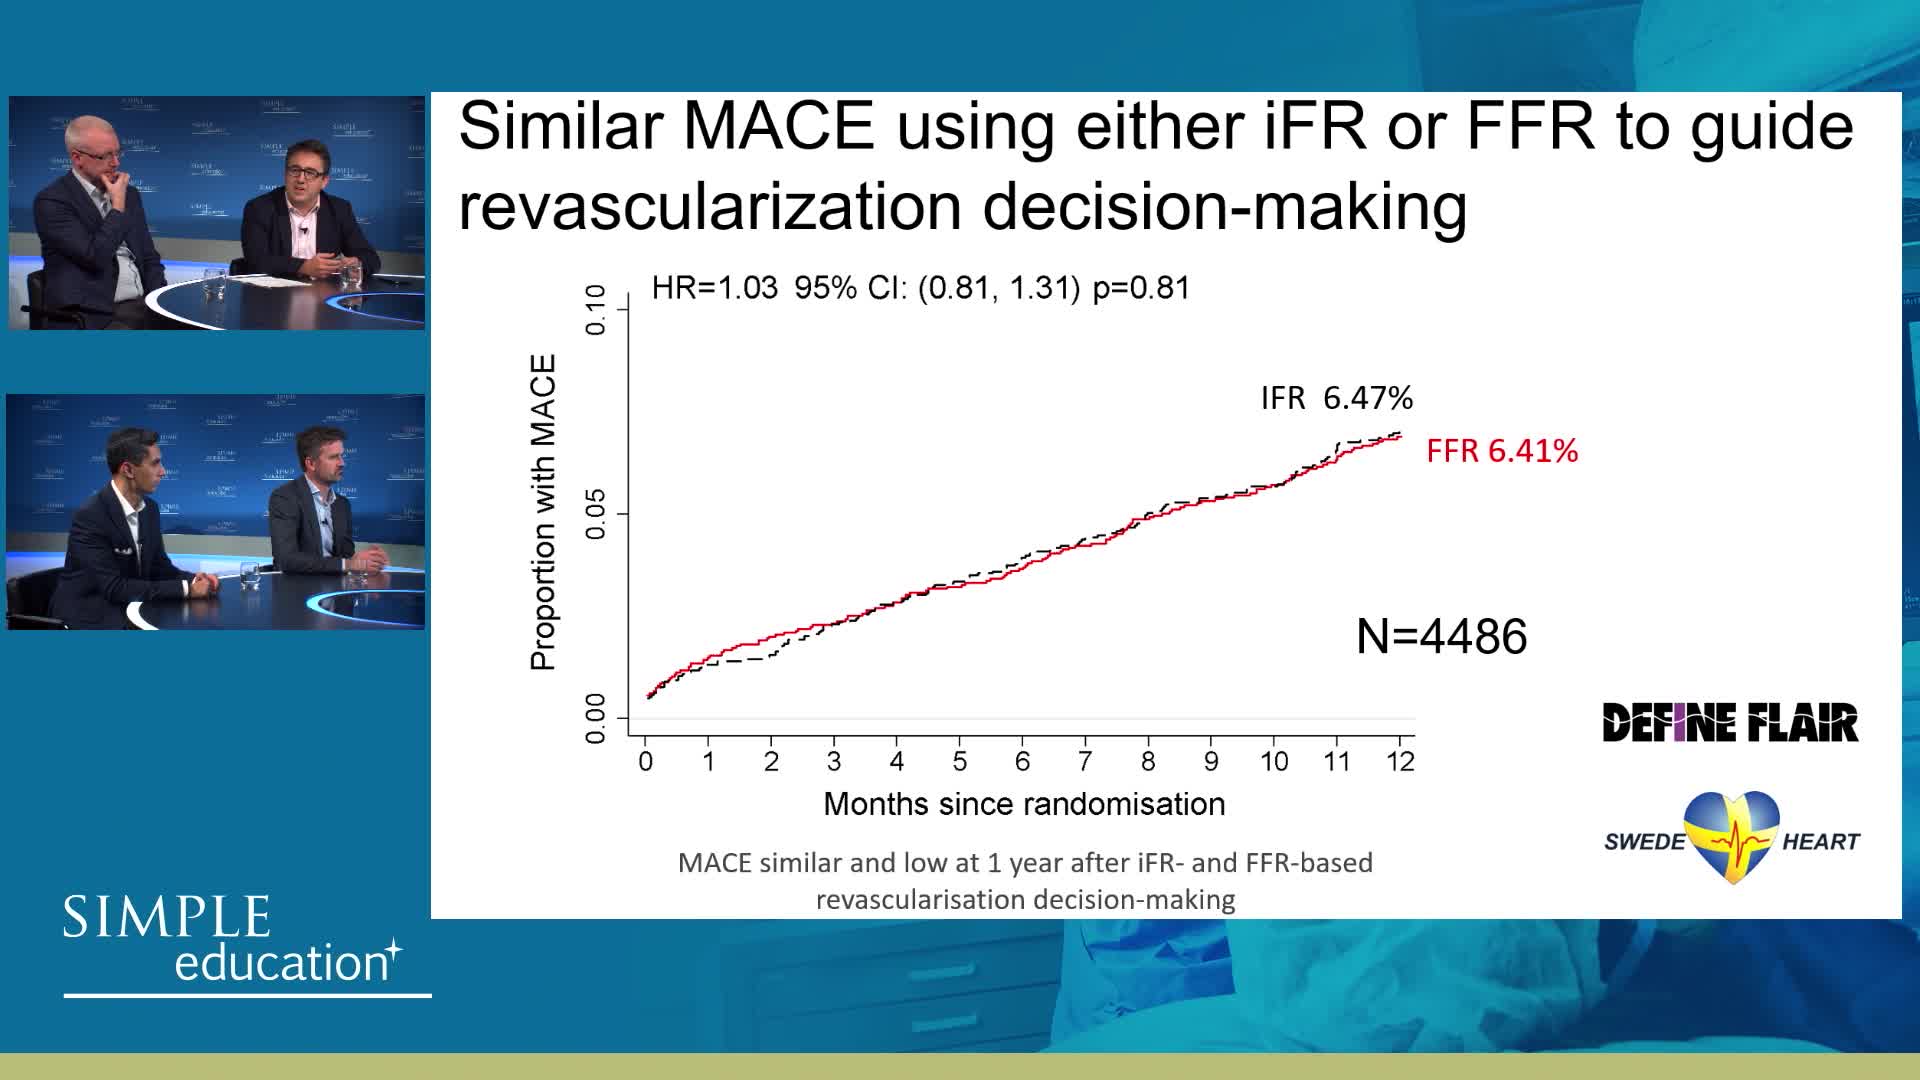

iFR or FFR in the LAD. What does the clinical outcome data tell us? - Dr Sayan Sen

20 year overview of clinical trial data to support the use of coronary physiology in revascularisation decision-making